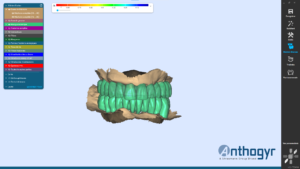

La réalisation des 2 bridges transvissés provisoires peut commencer sur le logiciel Exocad.

Impression 3 d des 2 bridges transvissés provisoire et pose.

3ème étape prise d’empreinte numérique immédiate avec transferts numériques Thommen, transfert sur Exocad et dessin des provisoires basé sur la morphologie initiale.

4 ème étape : impression du bridge provisoire en résine, nettoyage et collage sur embase titane.

5ème étape : bridge provisoire posé en bouche

Grâce à une bonne gestion du flux numérique, à la planification complète du cas, à la chirurgie full guided SMOP, à la prise d’empreintes numériques et l’impression du provisoire sur place, le patient est resté à peine 3h au cabinet et le cas a pu être géré en une seule intervention. Les profils d’émergence et contours gingivaux ont pus être préservés.